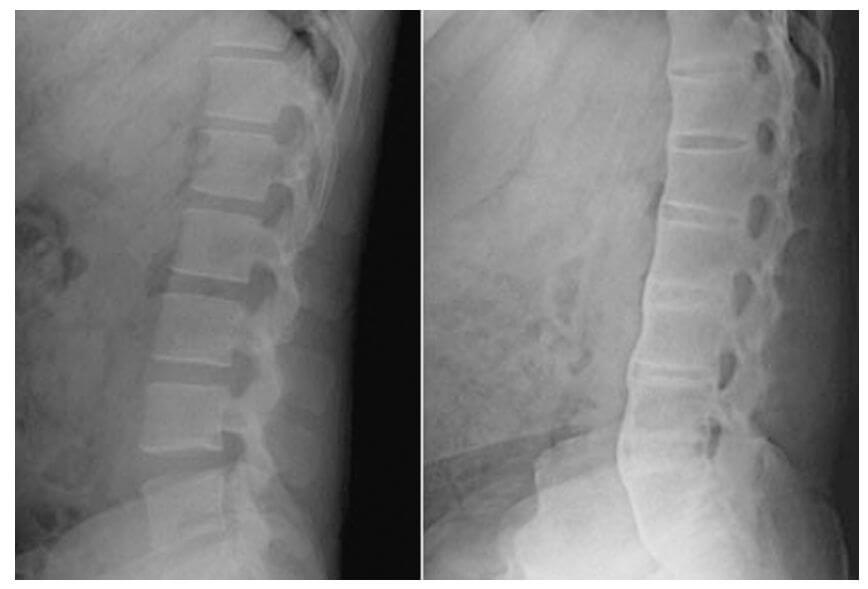

증상에 대한 문진 및 검진 그리고 방사선 검사로 강직성 척추염을 진단하게 됩니다.

또한 뼈 스캔(bone-scan), 컴퓨터 단층촬영(CT), 자기 공명 영상(MRI) 등을 촬영하거나 혈액검사를 통해 HLA-B27 항원 존재 유무로 판단할 수 있습니다.